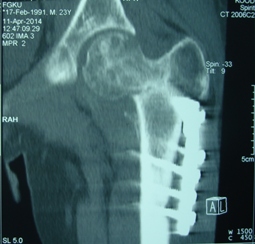

Уважаемые коллеги, приношу извинения за перерыв в работе -

был в командировке. За это время больному сделали КТ и,  сегодня,

снимки. Укорочение конечности - 1-1,5 см, ШДУ-115 градусов, замедленная консолидация,

остеопороз.

Вопрос о тактике дальнейшего ведения пациента (напоминаю, возраст 19

лет)?